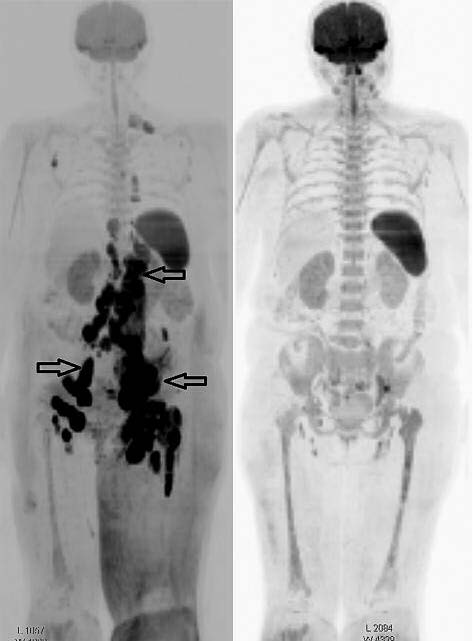

Шести из 15 пациентов после 4 курсов противоопухолевой терапии повторно выполнено КТ, МРТ-ДВИ-ВТ и ПЭТ/КТ. У 4 (из 6) больных достигнуто значительное сокращение размеров опухоли (не менее 80% от исходных размеров). Примеры визуализации динамики уменьшения размеров опухоли представлены на рис. 1, 2.

Рис. 2. Диффузионно-взвешенные изображения (импульсная последовательность, STIR) методом МРТ-ДВИ-ВТ больной ФЛ до (слева) и после (справа) проведения 4 курсов ПХТ.

Стрелками указаны конгломераты увеличенных лимфатических узлов и инфильтрация костного мозга проксимальной части левой бедренной кости. После 4 курсов ПХТ определяются регресс конгломератов лимфатических узлов и патоморфоз костного мозга левой бедренной кости (также отмечается регресс отека подкожно-жировой клетчатки левой нижней конечности).